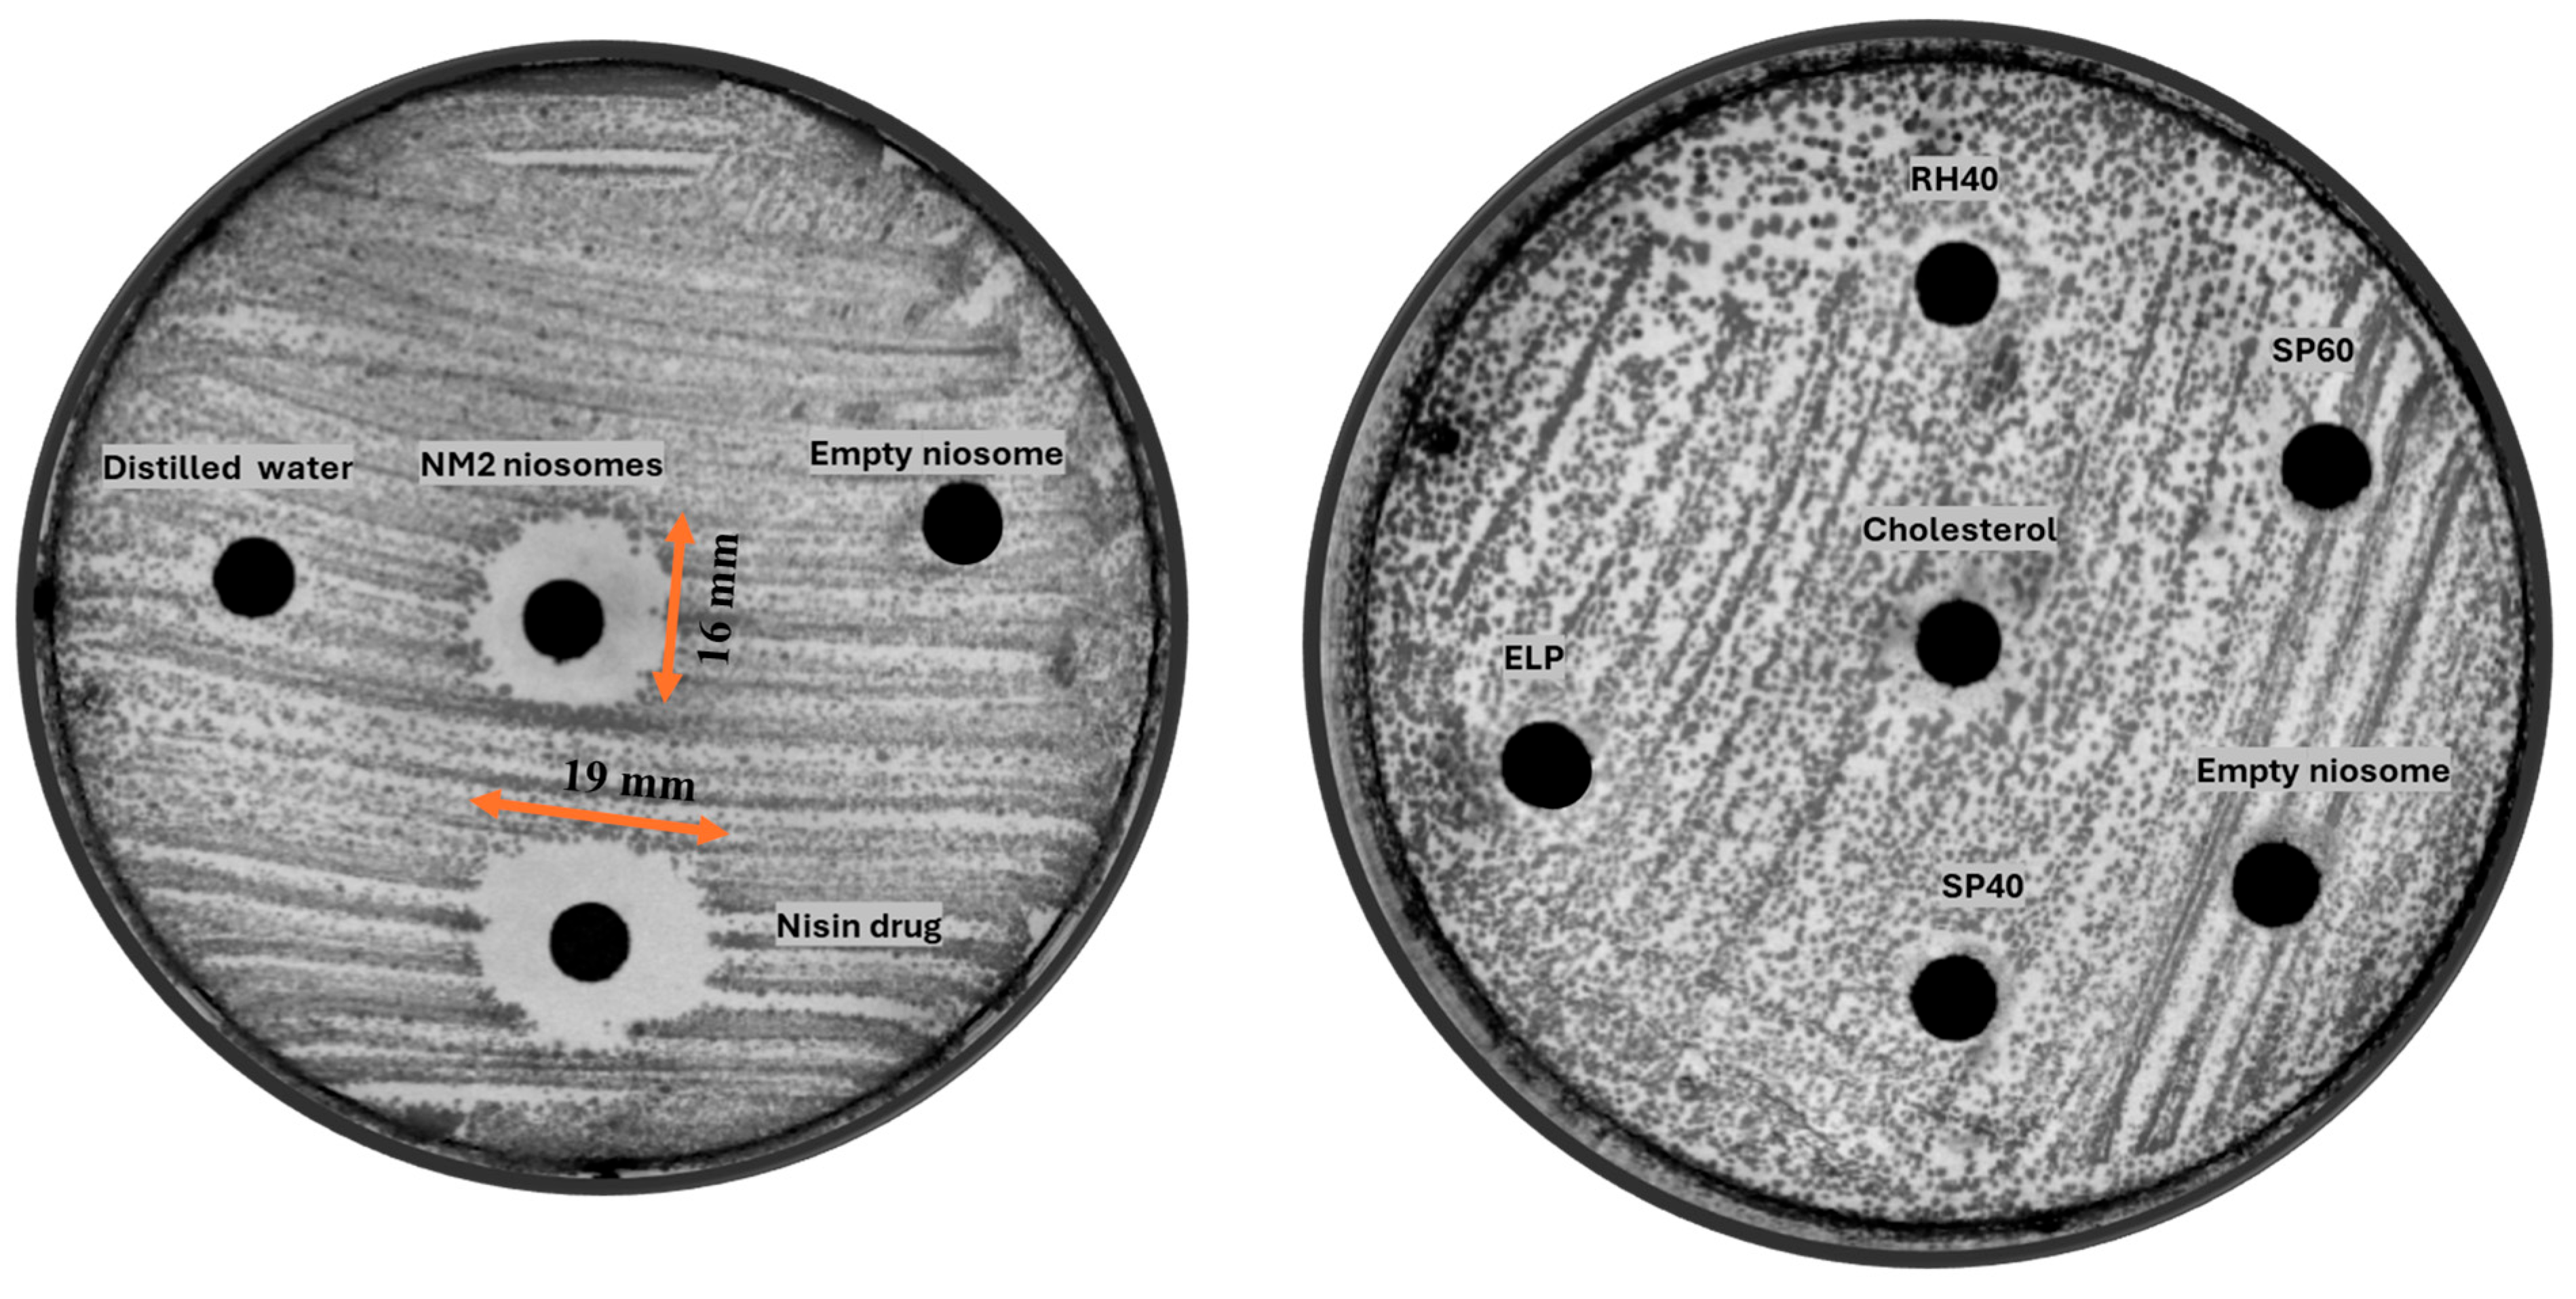

4.4. Antibiotic Assay Using an Agar Diffusion Method

5.2. Antimicrobial Activity